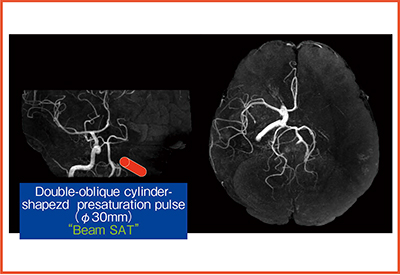

また,脳血流動態を選択的に観察するため,日立メディコ社と共同でselective MRAを開発した。“Beam SAT”という特殊なプレサチュレーションパルスを目的血管の近位部に照射することで,その灌流領域の血流信号を消去することができる(図7)12)。CEAやCASの術前における,Willis動脈輪を介した側副血行路の評価などに用いている。

図7 Beam SAT

文献12)より引用転載